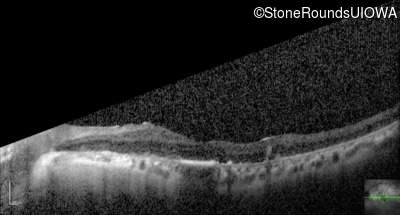

Optical Coherence Tomography - Right - 20/80

Exemplar / OCT Stack